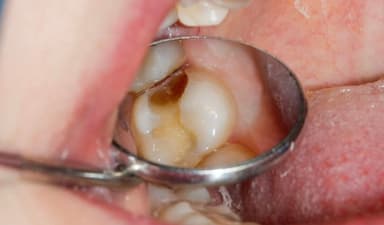

– Răng xuất hiện các lỗ nhỏ rồi lớn dần. Có thể cảm nhận được bằng lưỡi ở những vị trí khó nhìn thấy. Những vùng bị sâu có màu nâu hoặc đen.

– Các rãnh răng hàm chuyển màu là dấu hiệu sớm, cảnh báo sâu răng